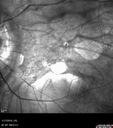

76 year old female with gradually declining vision: VA 20/32 OD; 20/40 OS

Myopic Degeneration - Inferior staphyloma with severe atrophy401 views76 year old with gradual vision loss. 20/32 OD; 20/40 OS00000